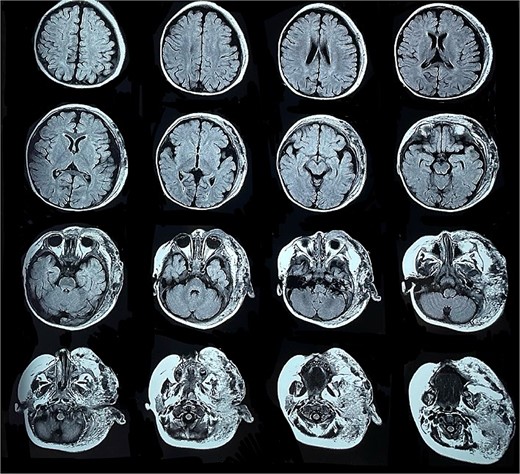

Six months later, the patient developed fever and severe edema that prevented the opening of the left eye, resulting in decreased overall tolerance. Laboratory results showed leukocytosis, severe thrombocytopenia (platelet count of 6000), and a positive C-reactive protein test. Physical examination revealed an irritable and lethargic patient with a 15 × 20 cm red mass with irregular borders (Fig. 1). An angioresonance was performed, revealing a hemangioma on the left hemiface that infiltrates muscle planes, the left parotid gland, and the auricular pavilion, ~10.7 × 6.6 × 13 cm in size, with possible vascularization from branches of the external carotid artery (Figs 2 and 3), leading to the diagnosis of KMP.

Angioresonance with evidence of a hemangioma on left hemiphase (coronal plane).